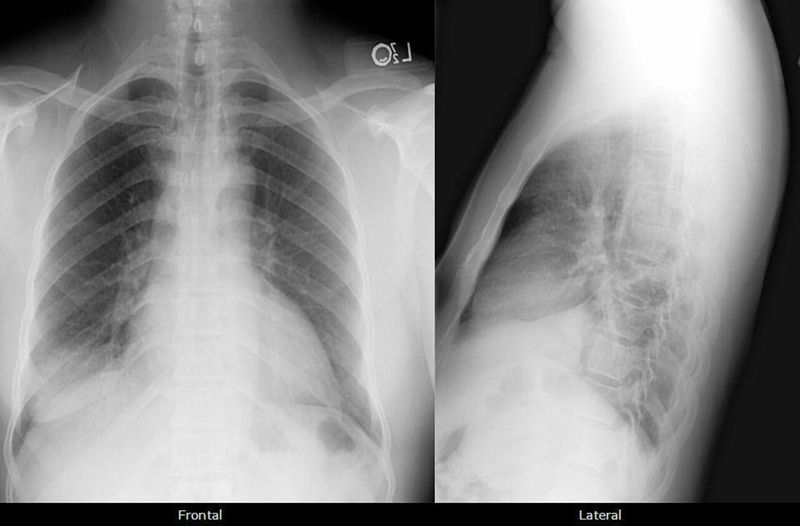

What are you find it and diagnosis please

R sided lower lobe consolidation ? Pneumonia

Where do you see the consolidation?? Is it at the in the lower rt lobe?! I wonder if it is pleural effusion?!!